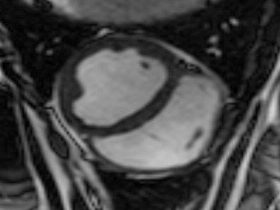

Easy-Trigger ist ein Medizinprodukt für die Herz- und Gefäßbildgebung in der Magnetresonanztomographie (MRT), das bifunktional bei Ungeborenen und Erwachsenen eingesetzt werden kann. Als weltweit erstes und einziges MRT-taugliches Doppler-Ultraschallgerät ermöglicht es erstmals Kombinationsuntersuchungen von MRT und Ultraschall. Der Ultraschallkopf wird auf dem Bauch oder über dem Herzen des Patienten platziert. Es ermöglicht erstmals die zeitliche Abstimmung der Herzaktion von ungeborenen Kindern mit dem MRT und damit MRT-Untersuchungen des kindlichen Herzens. Des Weiteren kann es zur Überwachung der Ungeborenen bei MRT-Untersuchungen von Schwangeren eingesetzt werden. Durch die Verwendung der Doppler-Ultraschall-Technik ist die Anwendung am Erwachsenen im Vergleich zum EKG robuster, einfacher und sogar bei höheren Feldstärken einsetzbar, bei denen das EKG nicht mehr zuverlässig arbeitet.